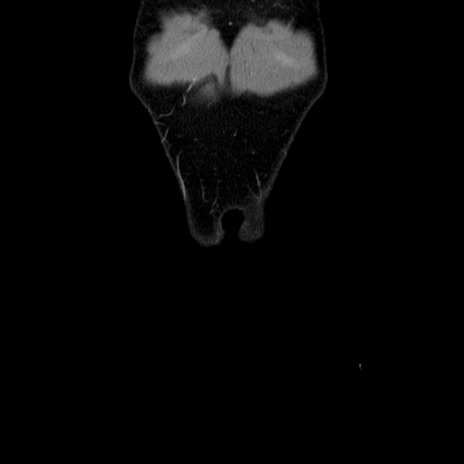

症例36(冠状断像)

【症例】20歳代 男性

【主訴】心窩部痛

【現病歴】今朝より上腹部痛あり。一旦軽快していたが再度出現したため救急要請。昨日夕に白身の魚を含む刺身を食べた。

【身体所見】BP 136/89mmHg、HR 74/min、BT 37.0℃、腹部:膨満、軟、心窩部に圧痛あり。反跳痛なし、筋性防御なし、腸雑音やや亢進あり。

【データ】WBC 17700、CRP 0.48